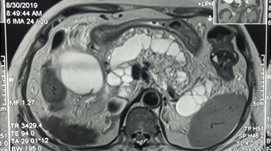

Bí tiểu cấp do chèn ép chùm đuôi ngựa trên bệnh nhân thoát vị đĩa đệm cấp: Báo cáo 2 trường hợp lâm sàng

ThS. Đinh Thị Phương Hoài, ThS. BSCKII. Nguyễn Thanh Minh, ThS. Nguyễn Vĩnh Lạc, BSNT. Trần Thị Mai Diệu, PGS.TS. Nguyễn Khoa Hùng.

U Schwannoma chóp tủy khổng lồ gây yếu liệt hai chi dưới: Báo cáo trường hợp lâm sàng

ThS. Đinh Thị Phương Hoài, ThS. BSCKII Nguyễn Thanh Minh, ThS. Nguyễn Vĩnh Lạc